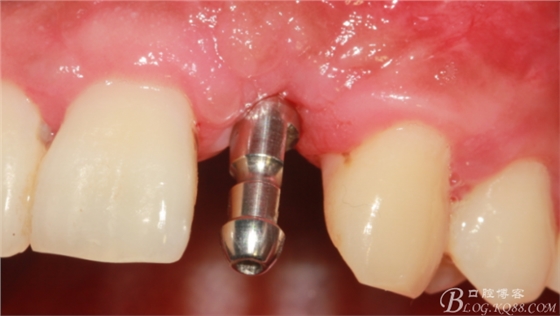

4個(gè)月后,唇側(cè)豐滿度尚可,與鄰牙之間齦乳頭完整。

保留齦乳頭翻小瓣。

翻開后驚喜的發(fā)現(xiàn),術(shù)區(qū)成骨非常好,去除部分骨才暴露那顆長(zhǎng)鈦釘。

取出影響種植入路的長(zhǎng)鈦釘。